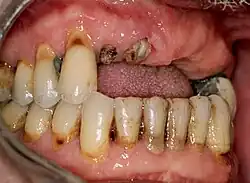

Zahnverlust

Wurzelreste der Zähne 11, 12